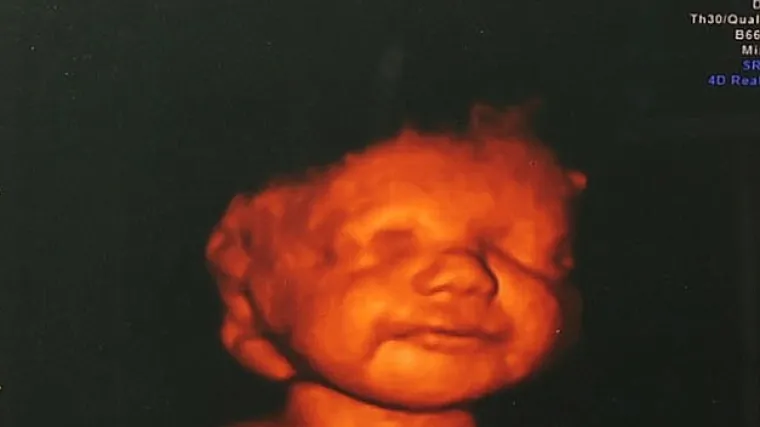

Kada je Katyia Rowe (26) iz britanskog Shropshirea saznala da će se njena beba roditi s oštećenjem mozga, odlučila je ipak roditi svoje dijete nakon što je vidjela njegov smiješak na slici ultrazvuka, javlja Daily Mail. Liječnici su nesretnoj ženi kazali kako se mozak njenog djeteta nije formirao do kraja i kako beba vjerojatno nikad neće moći hodati ni pričati te kako će trebati 24-satnu njegu do kraja života. Nakon što je vidjela lice sina kojeg su ona i njen partner Shane nazvali Lucian, odlučila je omogućiti mu da vidi svjetlo dana. Beba je umrla devet sati nakon što je rođena, no svoje posljednje minute provela je u narjučju majke. "To je bio najsretniji trenutak mog života. Lucian je već mogao umrijeti unutar mene, ali izdržao je dovoljno kako bi upoznao svoje roditelje", izjavila je Katyia.